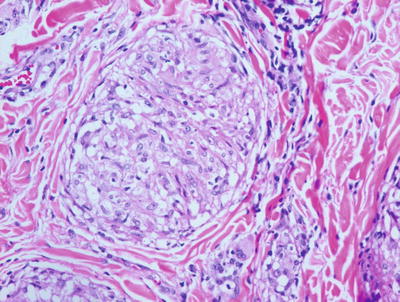

6.6.2 Histology

True rheumatoid nodules are rare in children and histologically indistinguishable from subcutaneous granuloma annulare. One large or several smaller palisades of histiocytes are present around a central area of altered collagen (Figs. 6.22 and 6.23). In some cases, the collagen demonstrates an accentuated red color due to fibrin deposition. In other cases, there is a bluish tinge on account of mucin deposition. Clinical correlation is the only reliable way to make the proper diagnosis. In some patients with juvenile rheumatoid arthritis , the increased number of rheumatoid nodules has been associated with methotrexate treatment [65].

Fig. 6.22

Rheumatoid nodule demonstrates a large focus of eosinophilic collagen with a surrounding palisade of histiocytes in the deep dermis and subcutis

Fig. 6.23

The dense eosinophilia is due to fibrin deposition on the collagen bundles in rheumatoid nodules